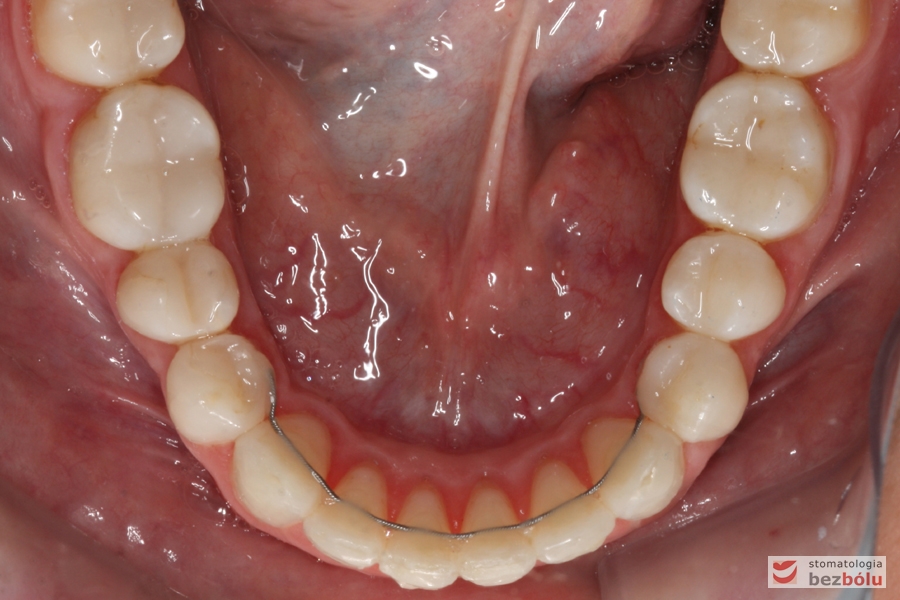

Retencja stała klejona od kła do kła

Uszeregowane siekacze dolne - tork dodatni

Uszeregowane siekacze dolne – tork dodatni